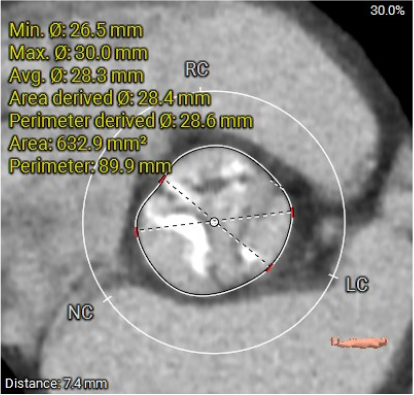

L28.4*R27.4*N28.8

SOVP89.9mm